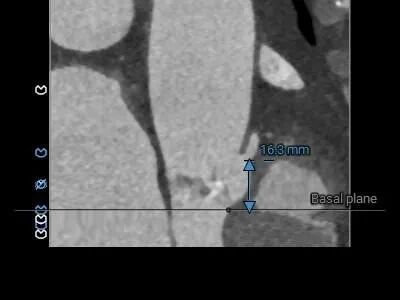

术前CT评估

• 三叶式主动脉瓣,瓣叶增厚,R-L交界增厚粘连,轻度钙化,钙化主要沿无冠窦瓣缘分布;LVOT近似直筒型;

• 瓦氏窦内径尚可,STJ小于30mm,升主动脉无扩张,瓣上40mm处测得约33.7mm;

主动脉根部评估